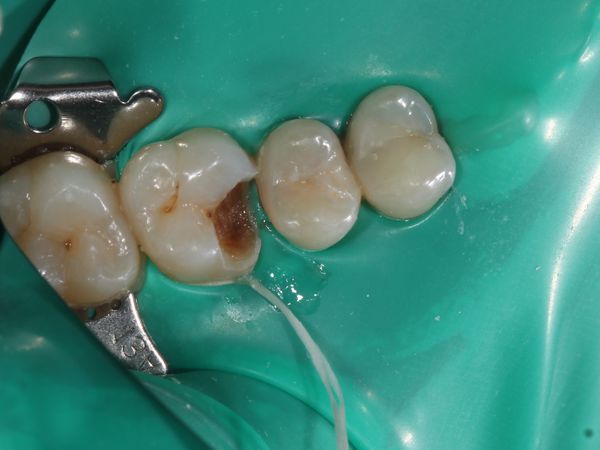

При осмотре зуба 1.6 обнаружена обширная кариозная полость на апроксимально-мезиальной поверхности (поверхность, которая прилегает к соседнему зубу и обращена к центру зубного ряда). Кариозная полость заполнена размягчённым дентином.

- Изоляция зуба 1.6 коффердамом. Коффердам представляет собой салфетку из латекса, которая позволяет изолировать нужный зуб для лечебных манипуляций.

- Препарирование кариозной полости и некрэктомия, что подразумевает раскрытие полости и удаление патологически изменённых эмали и дентина.

- Контроль препарированных тканей кариес-маркером (жидкостью, которая окрашивает участки зуба, поражённые кариесом).